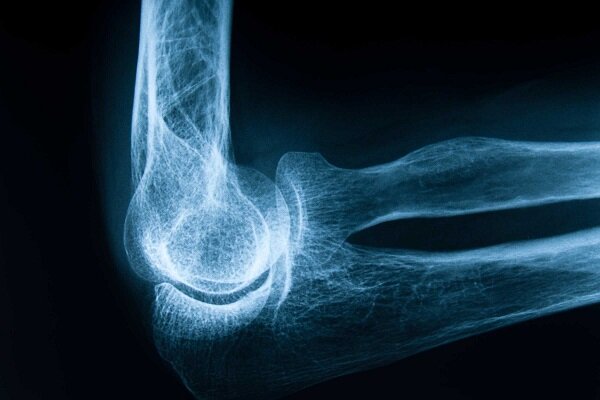

به گزارش خبرگزاری مجله آرونو، پوکی استخوان یا استئوپروز، یک بیماری مزمن و پیشرونده است که با کاهش تراکم و کیفیت بافت استخوانی، ساختار استخوان را شکننده و آسیبپذیر میکند؛ این بیماری اغلب بدون علامت بالینی مشخص پیشرفت میکند و تا زمان بروز شکستگی، ممکن است فرد از وجود آن بیاطلاع باشد. شکستگیهای ناشی از پوکی استخوان، بهویژه در نواحی لگن، ستون مهرهها و مچ دست، میتوانند منجر به درد مزمن، ناتوانی حرکتی، بستری شدن طولانیمدت و حتی افزایش خطر فوت در سالمندان شوند و از این رو، پوکی استخوان نه تنها یک مشکل استخوانی، بلکه یک چالش جدی در سلامت عمومی محسوب میشود.

تشخیص زودهنگام پوکی استخوان از طریق سنجش تراکم استخوان با روش DXA (جذبسنجی دوگانه اشعه ایکس) امکانپذیر است، این تست تراکم استخوان را در نواحی حساس مانند لگن و ستون مهرهها اندازهگیری و خطر شکستگی را پیشبینی میکند و بر اساس توصیههای بینالمللی، زنان بالای ۵۰ سال، مردان بالای ۷۰ سال و افراد دارای عوامل خطر باید بهطور منظم تحت غربالگری قرار گیرند، همچنین بررسی سابقه خانوادگی، مصرف داروهای خاص و بیماریهای زمینهای در ارزیابی خطر فردی اهمیت دارد.